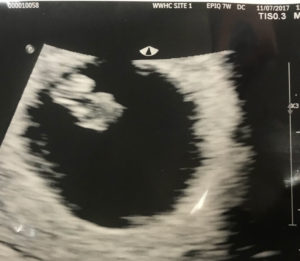

Age 44 And Pregnant After Tubal Clip Reversal!

Age 44 And Successfully Pregnant!

age-44-and-pregnant-after-tubal-reversal-surgeryI am 6 weeks 4 days gestation and the baby’s heart rate is 122!!

We are moving right along, Doc.

Kudos!!!!

Patient age: 44

Tubal ligation type: Tubal clips (clamps)

Patient hometown: Greensburg, Pennsylvania